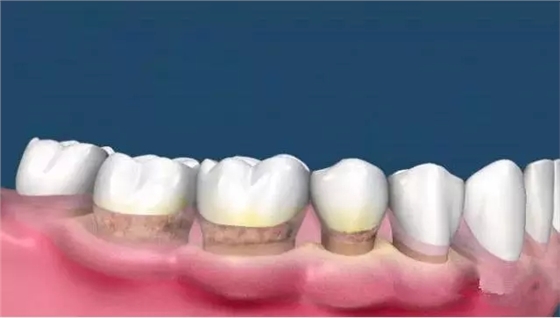

這時候很多人會發(fā)現(xiàn),齦上潔治和齦下刮治之后,很多人會發(fā)現(xiàn)牙根暴露在外面,而且牙縫明顯。

這是因為洗牙前牙齒的縫隙是因為那些縫隙里面填滿了牙結(jié)石,舌頭舔上去感覺不到,當(dāng)結(jié)石清除后,縫隙就會顯露出來。

而牙結(jié)石的堆積導(dǎo)致牙齦的退縮、牙根的暴露和牙槽骨的吸收,牙槽骨吸收以后是沒辦法恢復(fù)的,所以等到很嚴(yán)重才來看牙醫(yī)的時候,問題也許無法彌補(bǔ)了。

目前醫(yī)生盡最大的努力為患者保住了能夠保留的牙齒,保留不了的牙齒只能拔掉,然后再做種植修復(fù)。所以說,如果我們自己能夠有定期檢查、潔牙的意識,也許結(jié)果就不會是這樣。